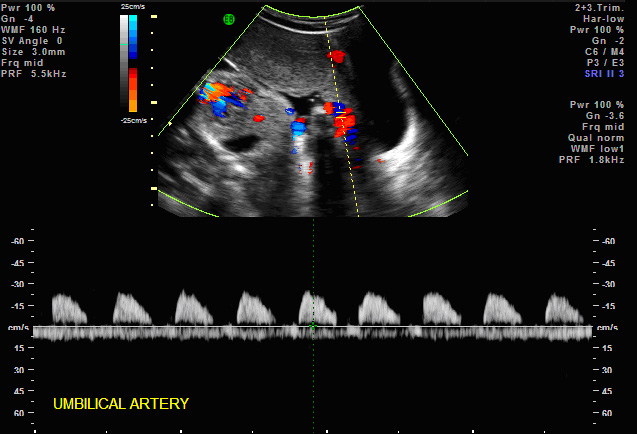

2. Umbilical Arteries — contains 40% of fetal ventricular output in both arteries. Traditionally the systolic flow to diastolic flow or S/D ratio has been used to monitor fetuses at risk. The umbilical Doppler has been particularly useful in managing patients with IUGR, preeclampsia, complicated medical illnesses (diabetes, lupus, etc). (Harrington K, Carpenter RG, Nguyen M, Campbell S. Changes observed in Doppler studies of the fetal circulation in pregnancies complicated by pre-eclampsia or the delivery of a small-for-gestational baby. I. Cross-sectional analysis. Ultrasound Obstet Gynecol 1995;6:19-28. & Pattinson RC, Norman K, Odendaal HJ. The role of Doppler velocimetry in the management of high risk pregnancies. Br J Obstet Gynaecol 1994;101:114-120. & Trudinger BJ, Cook CM, Giles WB, Ng S, Fong E, Connelly A, Wilcox W. Fetal umbilical artery velocity waveforms and subsequent neonatal outcome. Br J Obstet Gynaecol 1991;98:378-84) The ranges are gestationally determined with slightly higher S/D ratios (> 2.5-4.0) in early gestations prior to 24 weeks and the lower S/D ratios ( < 3.0) greater 24 weeks. The absence of end diastolic or reversed end diastolic flow is particularly worrisome. Most believe that the absence or reversed flow in the umbilical artery S/D ratio means a very high risk of stillbirth within 48-72 hours. (Karsdorp VH, Van Vugt JM, van Geijn HP, Kostense PJ, Arduini D, Montenegro N, Todros T. Clinical significance of absent or reversed end diastolic velocity waveforms in umbilical artery. Lancet 1994;344:1664-8 & Kurkinen-Raty M, Kivela A, Jouppila P. The clinical significance of an absent end-diastolic velocity in the umbilical artery detected before the 34th week of pregnancy. Acta Obstet Gynecol Scand 1997;76:398-404)

More recently, the pulsatility index (PI) has been used since it is not affected by the reverse or absence of end-diastolic flow. Reference ranges are used for the 5th and 95th percentiles. (Harrington K, Carpenter RG, Nguyen M, Campbell S. Changes observed in Doppler studies of the fetal circulation in pregnancies complicated by pre-eclampsia or the delivery of a small-for-gestational baby. I. Cross-sectional analysis. Ultrasound Obstet Gynecol 1995;6:19-28.)